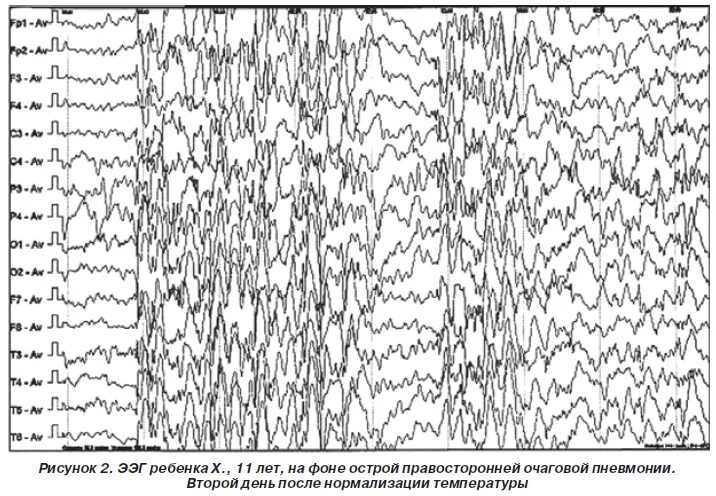

Простите, а что тот пацан должен был узнать в ЭЭГ?

Ну полосочки, и что?

Форма полос вообще никак не связана ни с какими образами внутри самой ЦНС.

ЧТО он там должен был узнать?

Это тест Роршаха что ли?

Смотрите какие разные графики по разным данным!

Ничего себе!

И что это значит????

Как такое может быть??? Это же разные графики по разным данным, как они могут быть разными?))))

99% пиздострадания, пару раз показывают какие-то графики, в конце "пришельцы" в виде дешевого cgi разростаются в виде веток деревьев во все стороны, люди бегут.